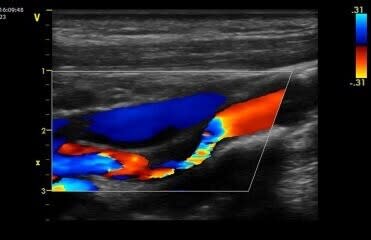

The carotid artery ultrasound scan is most frequently performed to detect stenosis , or narrowing of the carotid artery, a condition that substantially increases the risk of stroke. It is used as a general screening tool for patients over 45 years or if you have history of cardiovascular disease or at risk of stroke.

The scan will evaluate the shape, sizing, and outline, measuring also the blood flow velocities in the:

Common carotid arteries from their origin to bifurcation including intimal thickness

Internal and external carotid arteries

Vertebral arteries

Common pathology which can appear on the scan are plaque deposits and subsequent narrowing of the arteries particularly the internal carotid artery which supplies blood to the brain.